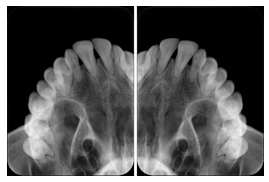

Intra-oral radiography typically involves acquisition of multiple images of various parts of the dentition. Many digital radiographic systems offer customized templates that are used for displaying the images in a study on the screen. These templates may also be referred to as mounts or view sets. The Structured Display Object represents a standard method of encoding and exchanging the layout and intended display of Structured Displays. A structured display object created in this manner could be stored with a study and exchanged with images to allow for complete reproduction of the original exam.

1. A patient visits a General Dentist where a Full Mouth Series Exam with 18 images is acquired. The dentist observes severe bone loss and refers the patient to a Periodontist. The 18 images from the Full Mouth Series along with a Structured Display are copied to a DICOM Interchange CD and sent with the patient to see the specialist. The Periodontist uses the CD to open the exam in his Dental Radiographic Software and consults via phone with the General Dentist. Both are able to observe the same exam showing the images on each user's display using the exact same layout.

Intra-oral Full Mouth Series Structured Display

Figure OO-1. Intra-oral Full Mouth Series Structured Display